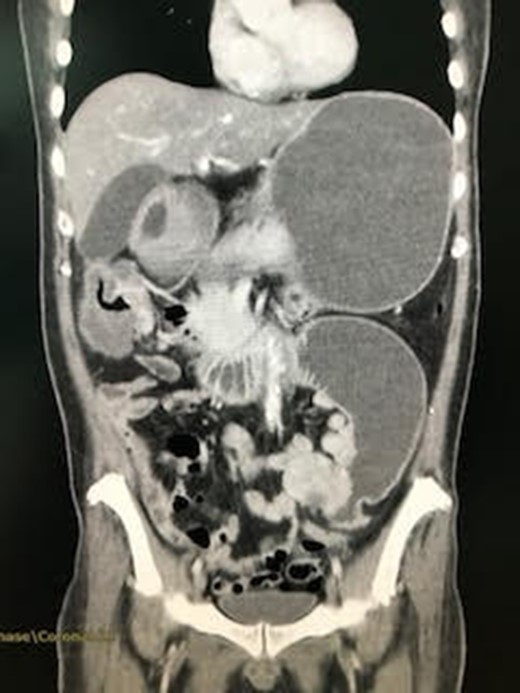

A Thai male patient, aged 46 years, presenting with chronic abdominal pain for 3 months. He frequently visited hospital in 3 months about chronic abdominal pain with unidentified cause—recurrent hyponatremia. He underwent upper gastrointestinal endoscopy and ultrasonography of upper abdomen but showed within normal limit of both examinations, so he was treated as chronic dyspepsia and symptomatic treated about hyponatremia but he still not improves. In admission day, he re-visited hospital with abdominal pain and his blood chemistry showed hyponatremic hypokalemic metabolic alkalosis, so gastric outlet obstruction was provisional diagnosis. Saline loading test showed delayed gastric emptying time. Patient was sent for computed tomography of abdomen because previous upper gastrointestinal endoscopy showed normal study. Computed tomography resulted in 5 cm long, enhanced wall thickening at duodenojejunal junction in left lower abdominal region, abutting adjacent sigmoid colon with preserved fat plane separation and markedly dilatation of the proximal duodenum and stomach is detected as in Fig. 1. The diagnosis of obstructed proximal jejunum was made and exploratory laparotomy was decided. In operative field, a 5 cm Cauliflower mass at proximal jejunum, 15 cm distal to ligament of Treitz, causing proximal duodenal dilatation and distal small intestines collapse was found as in Fig. 2. No liver, omental or peritoneal nodule was found. Radical segmental proximal jejunal resection (with 5 cm proximal and distal margins, with mesentery that vascular supplied resected jejunal segment) with primary small intestinal anastomosis was done. Operative time was 48 min and estimated blood loss was 50 mL. After operation, patient fully recovered but superficial surgical site infection was found and pus culture showed Proteus mirabilis and Escherichia coli. Pathologic examination showed well differentiated adenocarcinoma of jejunum with extension into perienteric fatty tissue, free all resected margins, and reactive hyperplasia of three lymph nodes. The diagnosis of Adenocarcinoma of the jejunum (pT3N0M0—stage II) was made and patient was referred to the oncologist for possibility of adjuvant therapy but the oncologist decided not to give patient adjuvant therapy. Patient remains healthy after 9 months of operation.

CT abdomen showed jejunal mass and proximal stomach and small intestine dilatation.